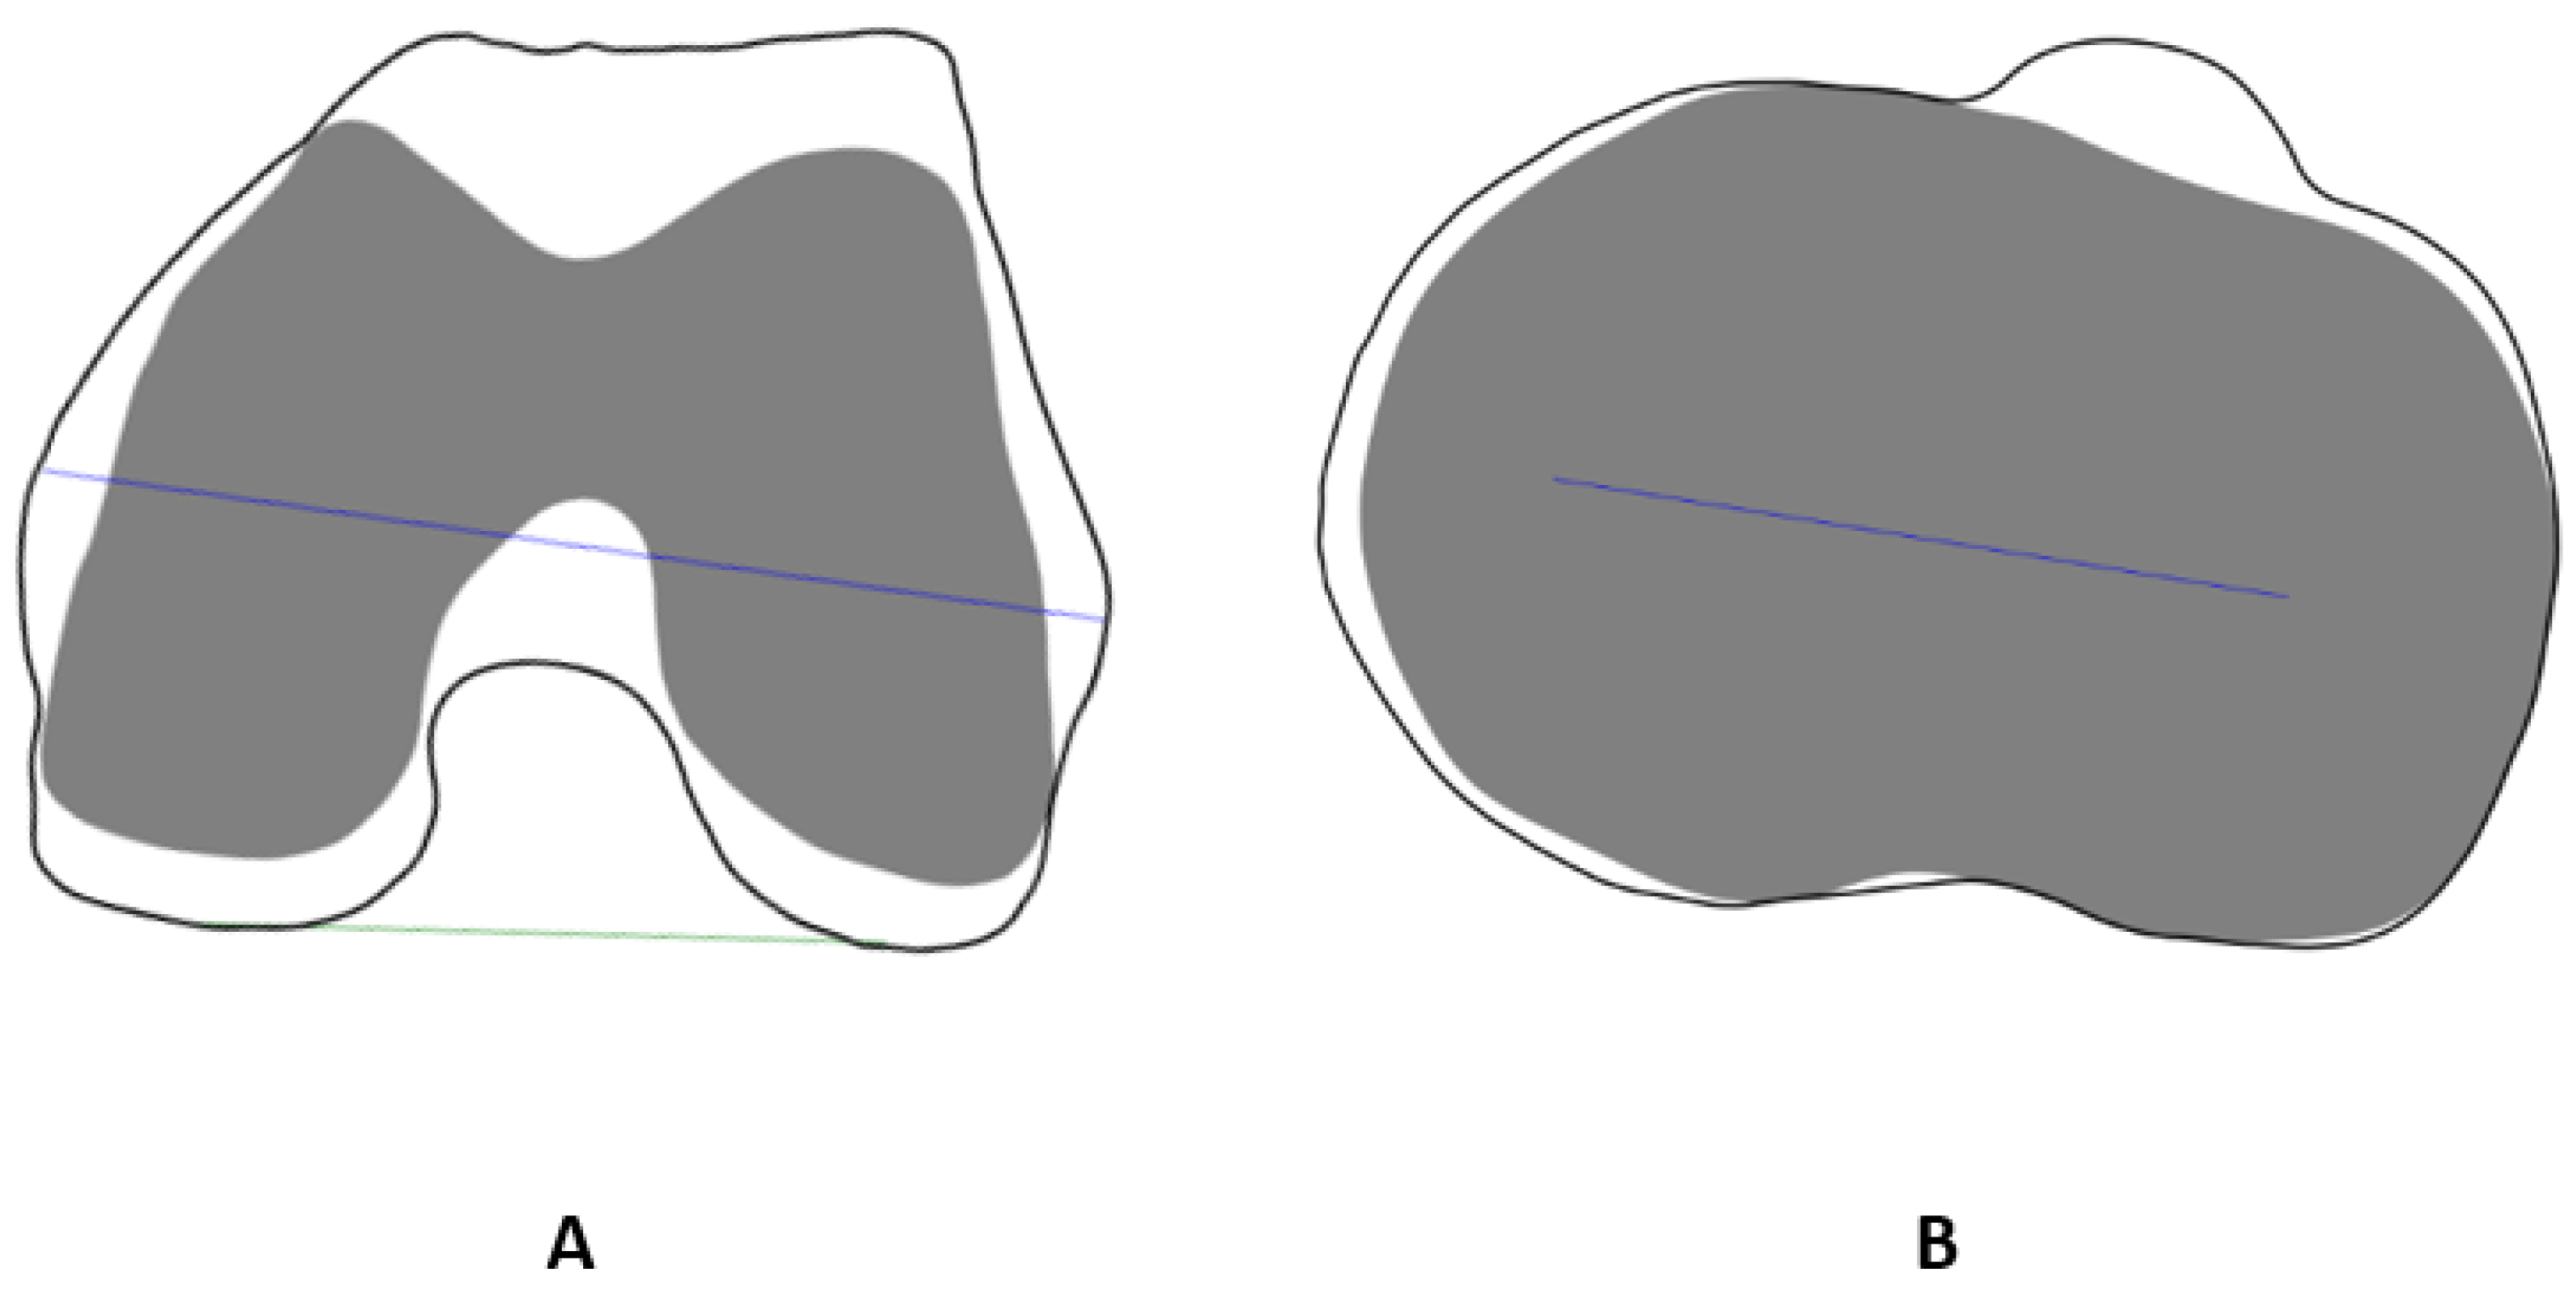

2. Materials and Methods